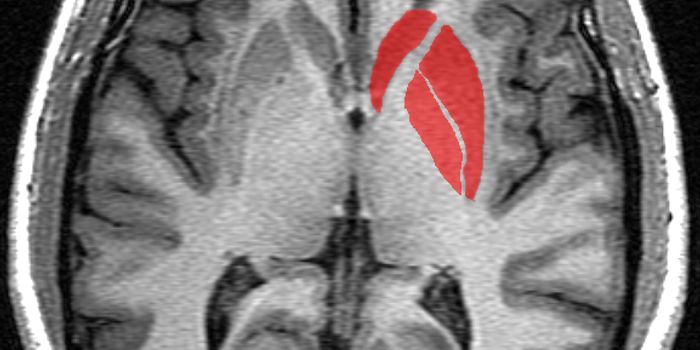

APR 24, 2015CancerThe simple act of thinking can accelerate the growth of many brain tumors.That's the conclusion of a paper in Cell publi ...

OCT 24, 2015ImmunologyMicroglia hold down the fort in the brain as the primary immune cell presence. When brain disease hits, they get rid of ...

JAN 07, 2022CancerThe blood-brain barrier (BBB) describes the complex vasculature network that delivers oxygen and nutrients to the brain. ...

MAY 04, 2016NeuroscienceRupture of small blood vessels in the brain can cause hemorrhagic stroke and brain microbleeds, and finding the fastest ...

FEB 26, 2016NeuroscienceStudies with genetically modified mice have unveiled additional connections between the immune system and Alzheimer&rsqu ...

MAR 18, 2016Health & MedicineScientists have developed a brain implant that can turn the patient’s immune system against Alzheimer’s dise ...